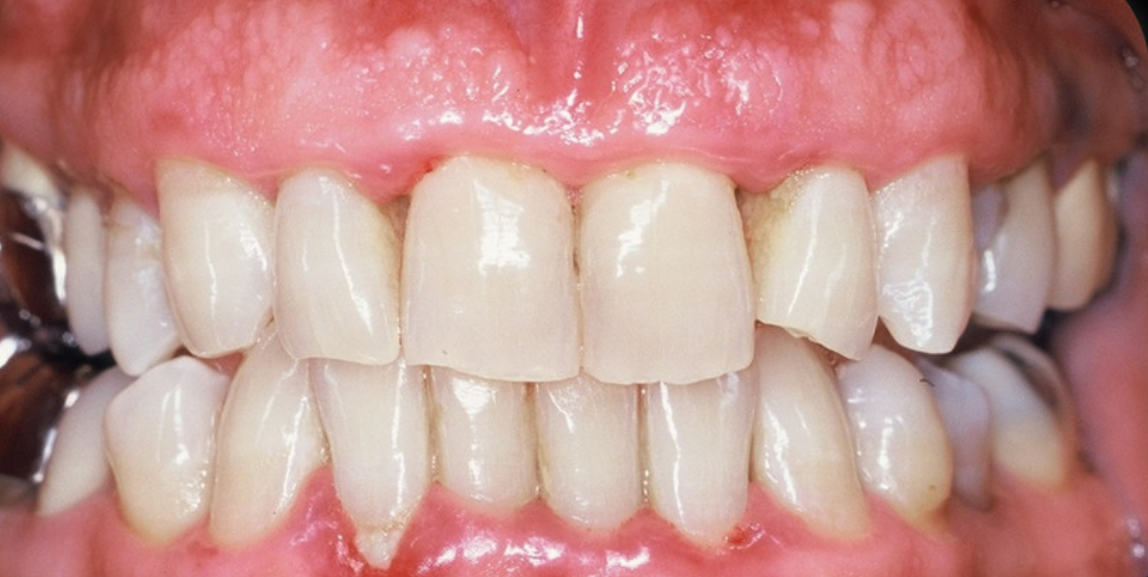

La gingivite hypertrophique : elle est différenciable des autres car elle conduit à un gonflement important de la gencive. Elle est très souvent le résultat de la prise de certains médicaments.

Cette maladie chronique est caractérisée par l’inflammation des gencives pouvant aller jusqu’à la rétractation des gencives et la destruction du tissu osseux.

Le déchaussement des dents correspond à une rétractation des gencives par rapport aux dents qui conduit à exposer les racines sous-jacentes. Différents facteurs peuvent favoriser cette maladie des dents : vieillissement, mauvaise hygiène bucco-dentaire, brossage trop vigoureux. Pour traiter le problème, le dentiste peut effectuer :